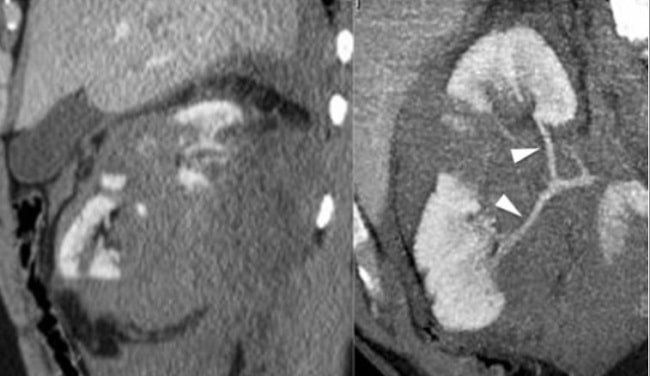

Diagnosis ruptur ginjal diawali dengan anamnesis, yaitu adanya riwayat trauma, pembedahan saluran kemih, dan abnormalitas ginjal sebelumnya perlu diketahui dari anamnesis. Modalitas pencitraan perlu dilakukan pada pasien dengan hematuria, seperti USG abdomen, serta CT scan abdomen dengan/tanpa kontras, dan angiografi.[2,4,5]